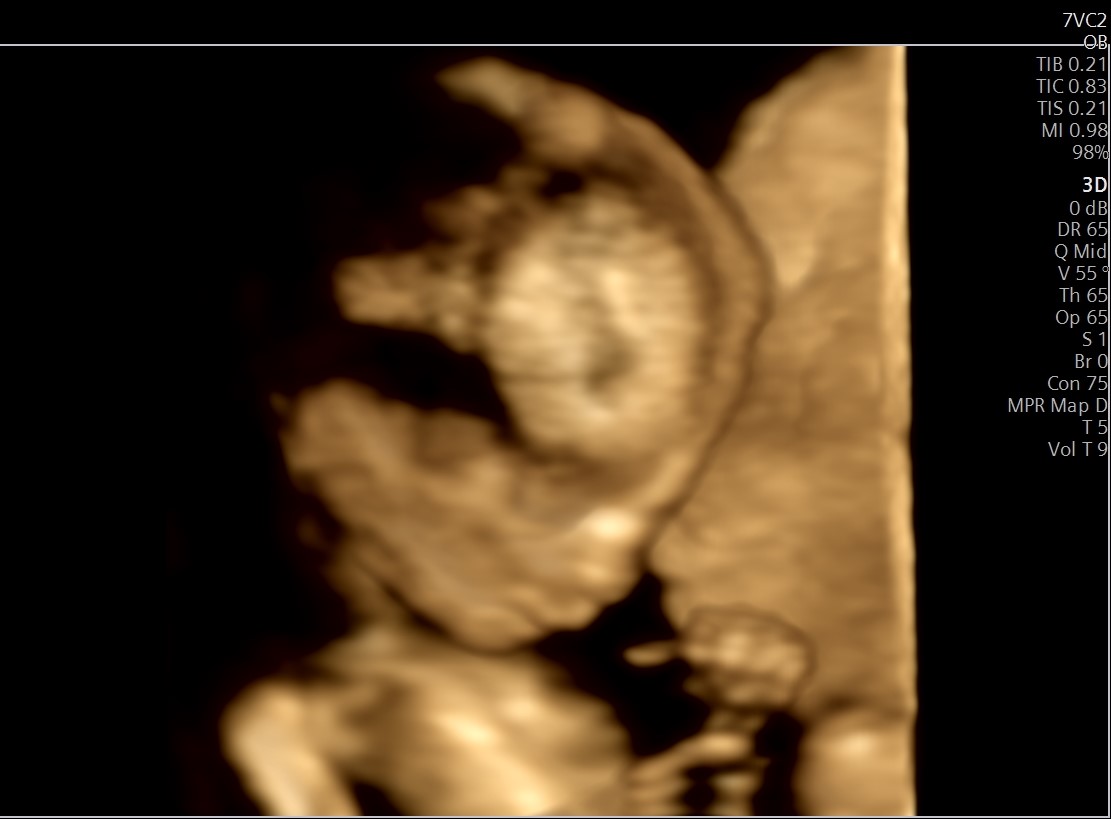

3d/4d echo

Je hoort en ziet het tegenwoordig overal! Een 3d en 4d echo. Mochten jullie in de zwangerschap al willen weten of jullie kindje meer op mama of papa (of grote broer of zus) lijkt dan is deze echo wat voor jou. De ‘leukste’ termijn voor een 3d en 4d echo is tussen de 26 en 32 weken zwangerschap. Op een 3d echo zul je jullie kindje in 3d kunnen zien. Met de 4d echo zijn deze 3d beelden live te zien. Alle dames die bij Lotus onder zorg zijn krijgen een kortingscode voor deze echo.

In de gallery zijn echo foto’s van kindjes van 10 t/m 36wk te zien! Neem een kijkje op de website van Echostudio Moon.